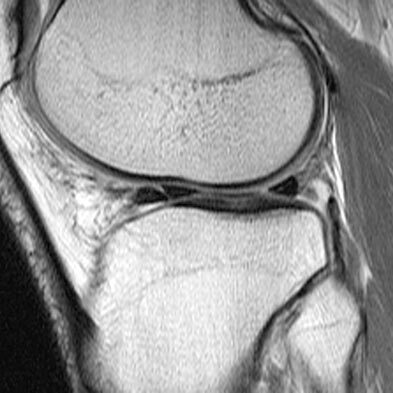

An 18-year-old man sustains a twisting injury to the left knee while playing football. An MRI scan is shown in Figure 48. What is the most likely diagnosis?

MRI scan shows a displaced, bucket-handle lateral meniscus tear. The sagittal view shows the typical “large anterior horn” sign, or “double meniscus” sign in which the displaced bucket-handle fragment appears just anterior to the native anterior horn of the lateral meniscus. The presence of the fibula on the sagittal view confirms this as the lateral compartment. The image is lateral and the cruciate ligaments are not visualized. The articular cartilage shown does not demonstrate an osteochondral lesion.